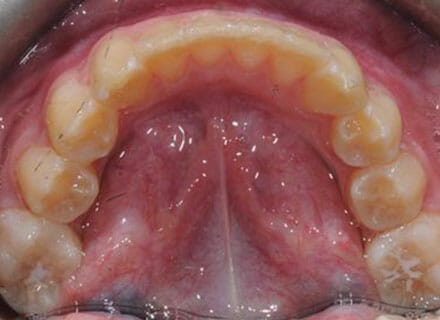

Fixing protruding teeth upper and lower and crowding – no extractions

this patient didn’t like the teeth because they pushed forwards and were sticking out and pushing out her lips. She thought that she looked like she had too many teeth and not enough space. In 12 months we pulled all the teeth back, pulled them together, and lined them all up. No teeth were extracted because we made room by expanding the jaws.